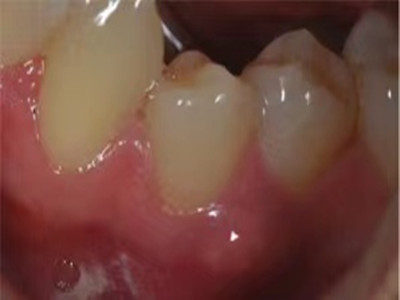

根尖囊肿是成牙组织囊肿中最常见者,多发生在上列切牙、尖牙或磨牙等牙根的唇面。由于根尖肉芽肿、慢性炎症的刺激,引起牙周膜内的上皮残余增生。增生的上皮团中央发生变性与液化,周围组织液不断渗出,逐渐形成囊肿,故亦可称根尖周囊肿。

根尖囊肿生长缓慢,病人多无自觉症状。口腔检查可见患牙有龋损或其他非龋性牙体病,或牙冠变色失去光泽。叩诊可有不适感,温度测验患牙无反应。囊肿大小不等,小囊肿不易被发现。囊肿发展较大时,可见根尖部隆起,扪诊时有乒乓球感,这是由于囊肿外围只有一层极薄的骨板存在。大囊肿还可压迫牙根,使邻牙移位。

根尖囊肿可由慢性根尖周肉芽肿或慢性根尖周脓肿等发展而来。因牙根感染、牙髓坏死,进而根尖周形成肉芽肿或脓肿,随后上皮细胞长入其内作为衬里形成囊肿内膜,病牙根尖突入囊肿腔内。增生的上皮团中央发生变性与液化,周围组织液不断渗出,逐渐形成根尖囊肿。